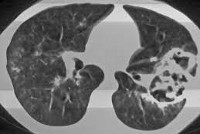

Основополагающую роль в установлении диагноза играют результаты рентгенологического обследования. Вместе с тем, стандартная рентгенография легких не всегда позволяет визуализировать небольшие полостные образования на фоне пневмонической инфильтрации. Поэтому при подозрении на абсцедирующую пневмонию целесообразно прибегать к проведению КТ грудной клетки. В случае формирования абсцесса легкого на снимках определяется толстостенное полостное образование с наличием характерного уровня жидкости и газа.

Основополагающую роль в установлении диагноза играют результаты рентгенологического обследования. Вместе с тем, стандартная рентгенография легких не всегда позволяет визуализировать небольшие полостные образования на фоне пневмонической инфильтрации. Поэтому при подозрении на абсцедирующую пневмонию целесообразно прибегать к проведению КТ грудной клетки. В случае формирования абсцесса легкого на снимках определяется толстостенное полостное образование с наличием характерного уровня жидкости и газа.